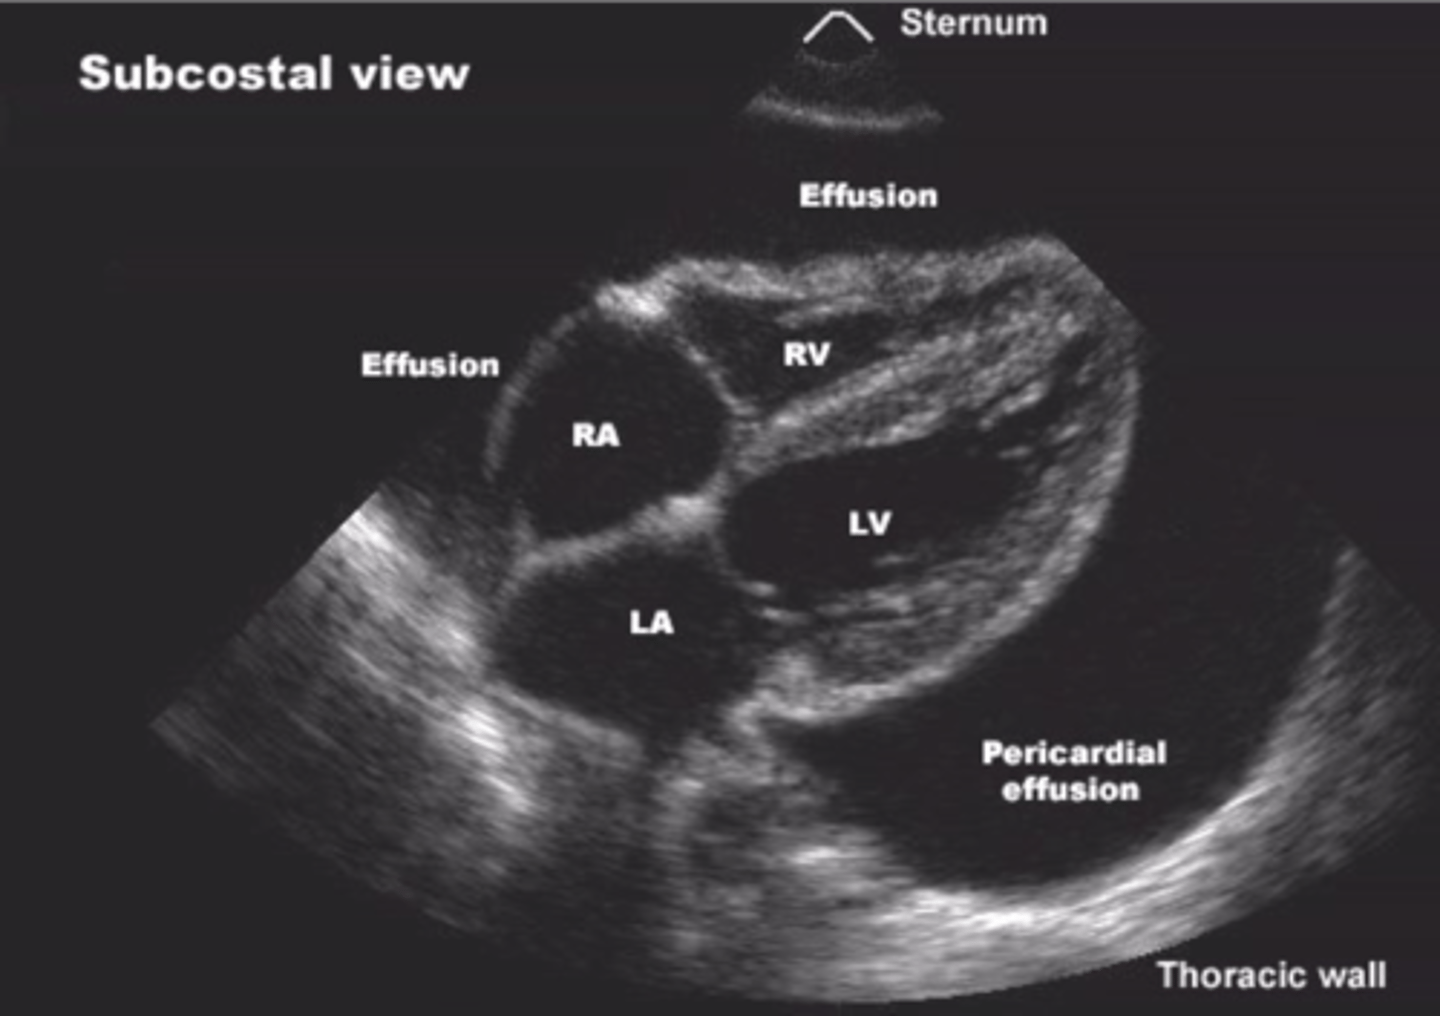

What are diagnostic ultrasounds used for?

View organs & evaluate motion (cardiology, OBGYN, GI, & vascular medicine)

Diagnostic ultrasound

<p>Echoes of the US beam bounce off interfaces between tissues with different acoustic properties</p><p>-Sends high-frequency sound into patient &amp; assesses strength &amp; time of returning echoes</p><p>-Echoes caused by changes in density</p>

What's an echocardiogram used to evaluate?

<p>Valves, pericardial fluid, pressures, wall motion, ejection fraction, &amp; masses</p>